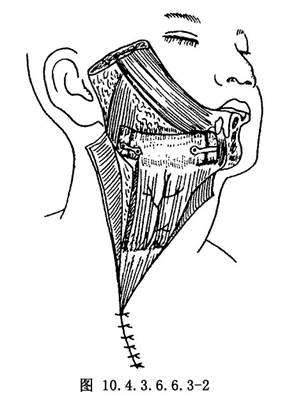

先將舌側口底黏膜與頰側黏膜縫合,使形成襯裏,充分沖洗傷口,而後將肌骨瓣的軟組織與口腔側黏膜固定數針,使之正確就位,而後修整兩側骨斷端,並分別與肌皮骨瓣上的肋骨成端端對合。用電鑽在各側相對部位各鑽兩孔,而後用不鏽鋼絲結紮或微型鋼板固定(圖10.4.3.6.6.3-2)。

胸大肌的肌蒂部,覆蓋在頸動脈竇部以替代失去的胸鎖乳突肌,肌層與臨近肌肉作間斷縫合固位,而後縫合頸部皮瓣的皮下組織和皮膚,置入負壓引流管引流(圖10.4.3.6.6.3-3)。